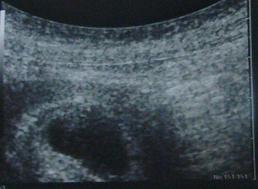

今日は病院へ行ってきました

そして、やっと出会えましたねぇ

この前は見えなかった赤ちゃんが

この黒いのが子宮

そして下の方にちょろっと小さく白い点が赤ちゃんです

それも実際に見たときには

ぴょろり~んぴょろり~んと心臓が動いてました

ああ、生きてるんだな~って

当たり前だけど

へへっ、やっと実感わきましたよ

さて、先生がいうには、もうすでに3ヶ月目に入ったばっかりだそうで